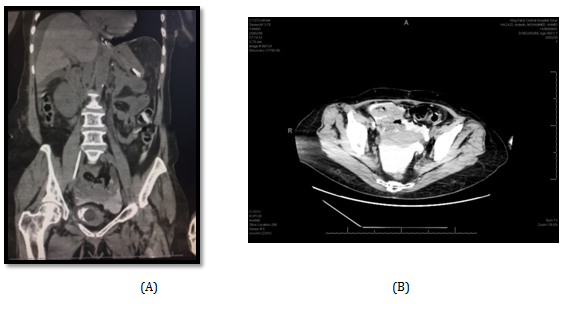

A 65 year old female referred from a peripheral hospital to the emergency comatosed, desaturated and intubated. Her relative gave history of long standing hypertension. On examination; patient was afebrile, intubated, Blood pressure was 160/100.Laboratory investigations were done and revealed a serum creatinine of 1990umol/l, BUN 74 mmol/l, serum K 6.3 mmol/l, Hb 8.2 gm, and WBCs 20110. Patient was admitted in ICU and diagnosed as uremic encephalopathy with pulmonary edema. Glasgow Comma Scale (GCS) was 8/15 and urethral catheter which was already placed drained 1000 ml/ 24 hours, turbid urine. Proper parenteral antibiotic was given according to culture and sensitivity test and patient underwent one session of hemodialysis(HD). Thereafter, serum creatinine dropped to 1002 mg/dl should be placed) BUN 54.3mmo/l and serum K 3.7 mmol/l. Non-contrast CT scan was performed combined with retrograde cystogram and showed mild bilateral backpressure, intra-abdominal free fluid collection and extravasation of contrast into the pelvis and abdominal cavity (Figure 3A & B).

Figure 3: Non-contrast CT Cystogram showing contracted bladder (A) and intraperitoneal fluid with extravasation of contrast into peritoneal cavity (A and B).